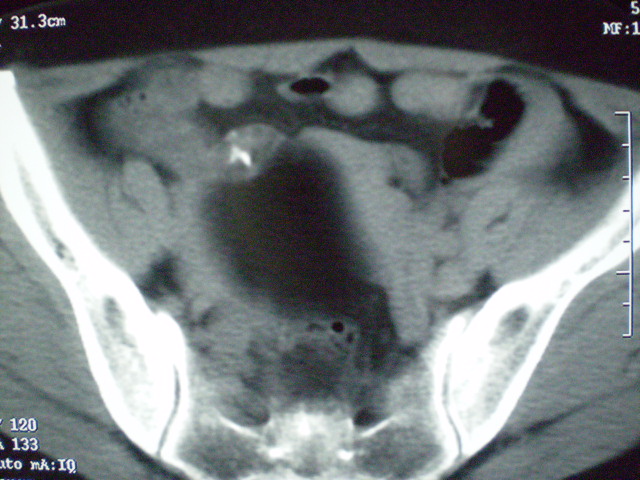

f 60y,b超提示脂肪瘤.[img][/img]

右侧附件囊性畸胎瘤,三种组织均见.

脂肪密度肿块,内可见团块状影,典型皮样囊肿

的确比较典型的畸胎瘤!不过,应该确切的说是盆腔畸胎瘤,右侧附件来源的可能性比较大。